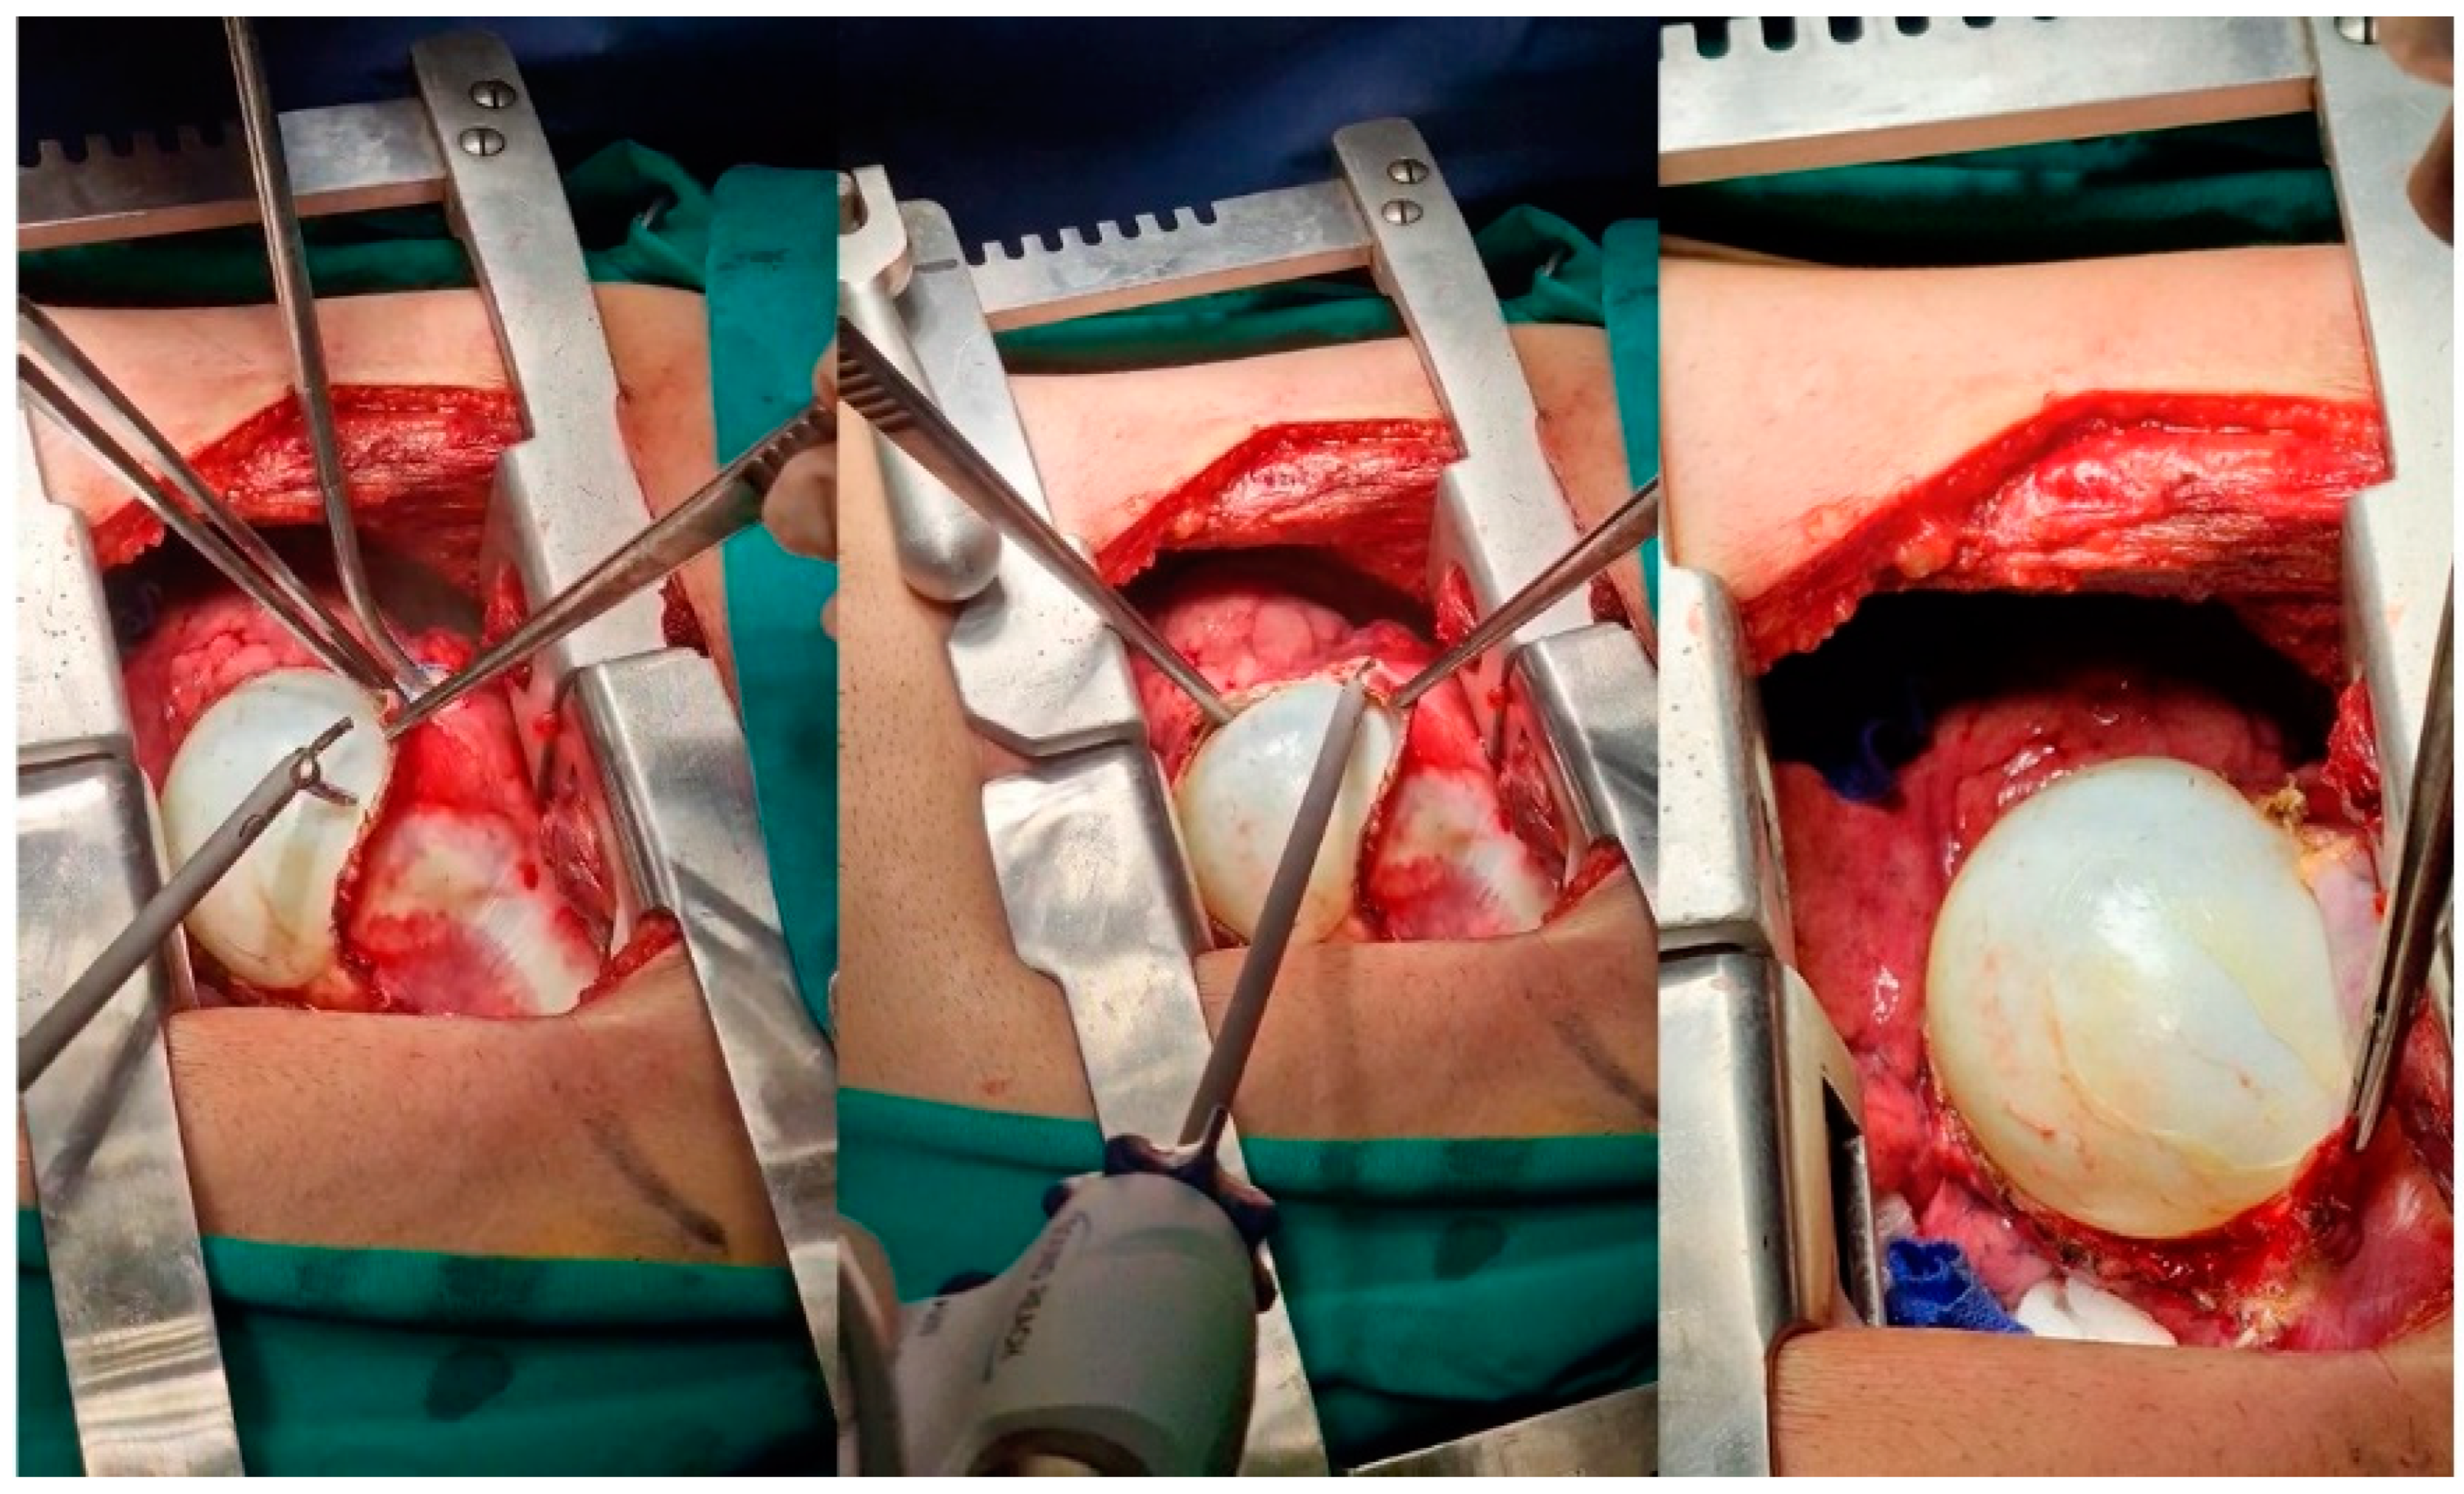

The uncomplicated large intraparenchymal pulmonary lesion. Typical diameters can exceed 15 cm. In such cases, wedge-excisions are unsuitable due to the size and a potentially central location. Instead, enucleation is indicated to spare parenchyma. The dissection of the cyst from the surrounding parenchyma is facilitated with a standard thoracoscopic energy device with ‘coagulate and cut’ functions and dissecting maneuvers, similar to adhesion lysis (Figure 8). Careful movements are required to avoid any rupture or spillage. Open bronchi should be recognized and ligated with nylon sutures 3-0 or 4-0 to prevent prolonged air leaks. Rarely, extra thoracic cysts may be misdiagnosed as soft tissue abscesses and percutaneously drained. Similarly, these cysts can be dissected free from the surroundings with an energy device (Figure 9).

Figure 8. Intraoperative images of patient 2 with pulmonary echinococcosis. An energy device performs dissection without rupture of a large intraparenchymal cyst.